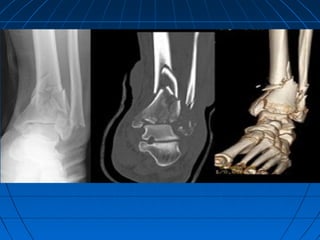

• CTCT

– Joint involvement,Joint involvement,

– Posterior malleolarPosterior malleolar

fracture pattern,fracture pattern,

– Pre-operativePre-operative

planning,planning,

– Evaluate hindfoot andEvaluate hindfoot and

midfoot if needed.midfoot if needed.